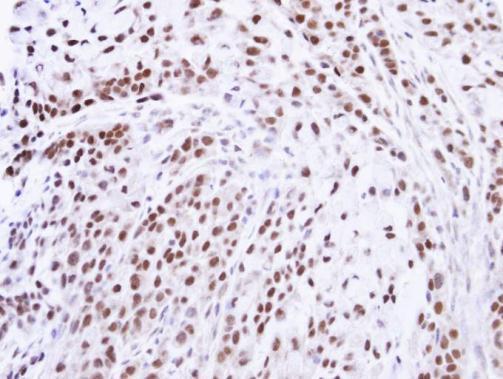

Supportive validation

- Experimental details

- Immunohistochemical analysis of paraffin-embedded A549 xenograft , using ZNF346(GTX111035) antibody at 1:100 dilution.